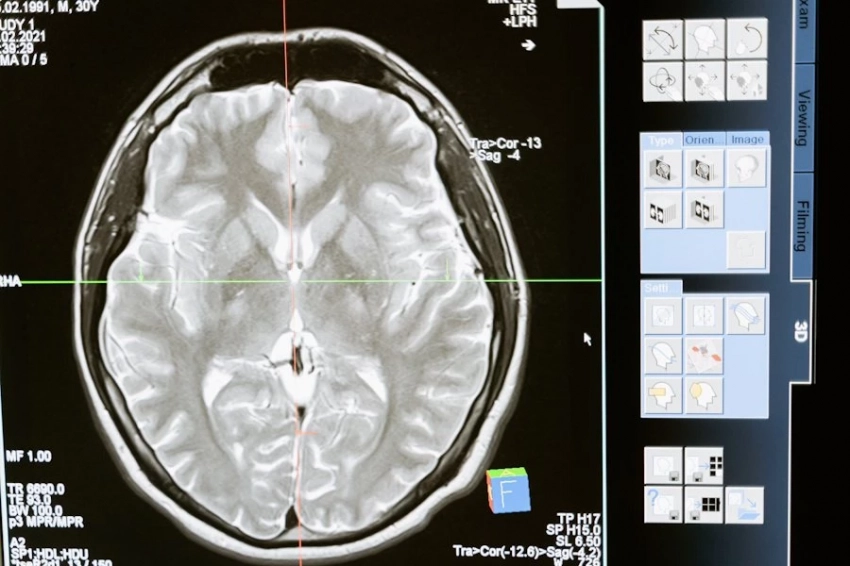

Alzheimer’s Association: ИИ рассчитал факторы старения мозга

Фото из открытых источников Командой исследователей из Каролинского института произведён анализ снимков мозга 70-летних испытуемых с использованием искусственного интеллекта. Главной целью было выяснить, каков реальный биологический возраст мозга каждого участника, как это коррелирует с состоянием здоровья, и...